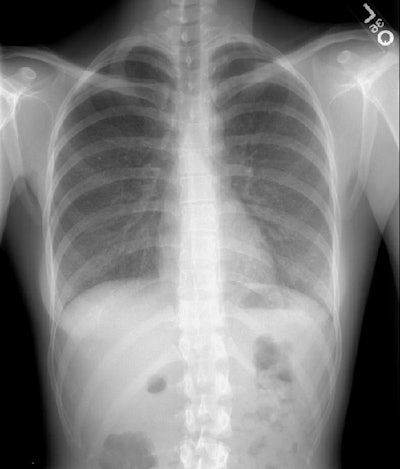

Extrinsic Allergic Alveolitis:

The patient was a middle aged female who had recently acquired several birds as pets. She had developed symptoms of progressive dyspnea and presented for evaluation. Her chest radiograph demonstrated ground glass opacity and a fine micronodular pattern predominantly involving the mid and lower lung zones (Click image to magnify). The patient sold her birds and her symptoms resolved following a course of corticosteroids.